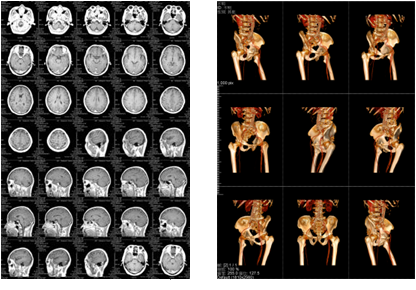

該三甲醫(yī)院放射科負(fù)責(zé)日常CT、核磁共振影像的輸出,平均的日打印量在1000張左右。在導(dǎo)入解決方案前,該放射科的影像輸出使用干式膠片打印傳統(tǒng)膠片,輸出設(shè)備價格不菲,而且傳統(tǒng)膠片價格更是高昂。另外,傳統(tǒng)膠片不能實現(xiàn)彩色輸出,醫(yī)生必須在背光板上進行診斷,膠片本身還含有重金屬等有毒物質(zhì),污染環(huán)境。為此,柯尼卡美能達向?qū)I(yè)供應(yīng)商采購了DICOM轉(zhuǎn)換服務(wù)器和符合醫(yī)院要求的打印膠片紙,可實現(xiàn)三維打印,打印的影像可直接在自然光下觀看,便于醫(yī)生診斷;膠片紙的成本是傳統(tǒng)膠片的三分之一而且不含毒物質(zhì),既節(jié)省成本又綠色環(huán)保。

膠片紙輸出樣張示意